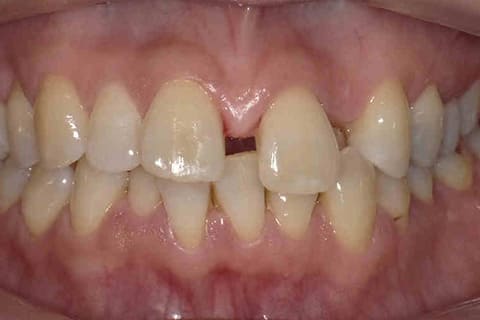

健康に美しく臨床実績集

虫歯や歯周病、事故などでの欠損、

噛めるようになりたい、見た目の美しさの追求など、

審美的に機能的に回復した治療経過報告症例です。